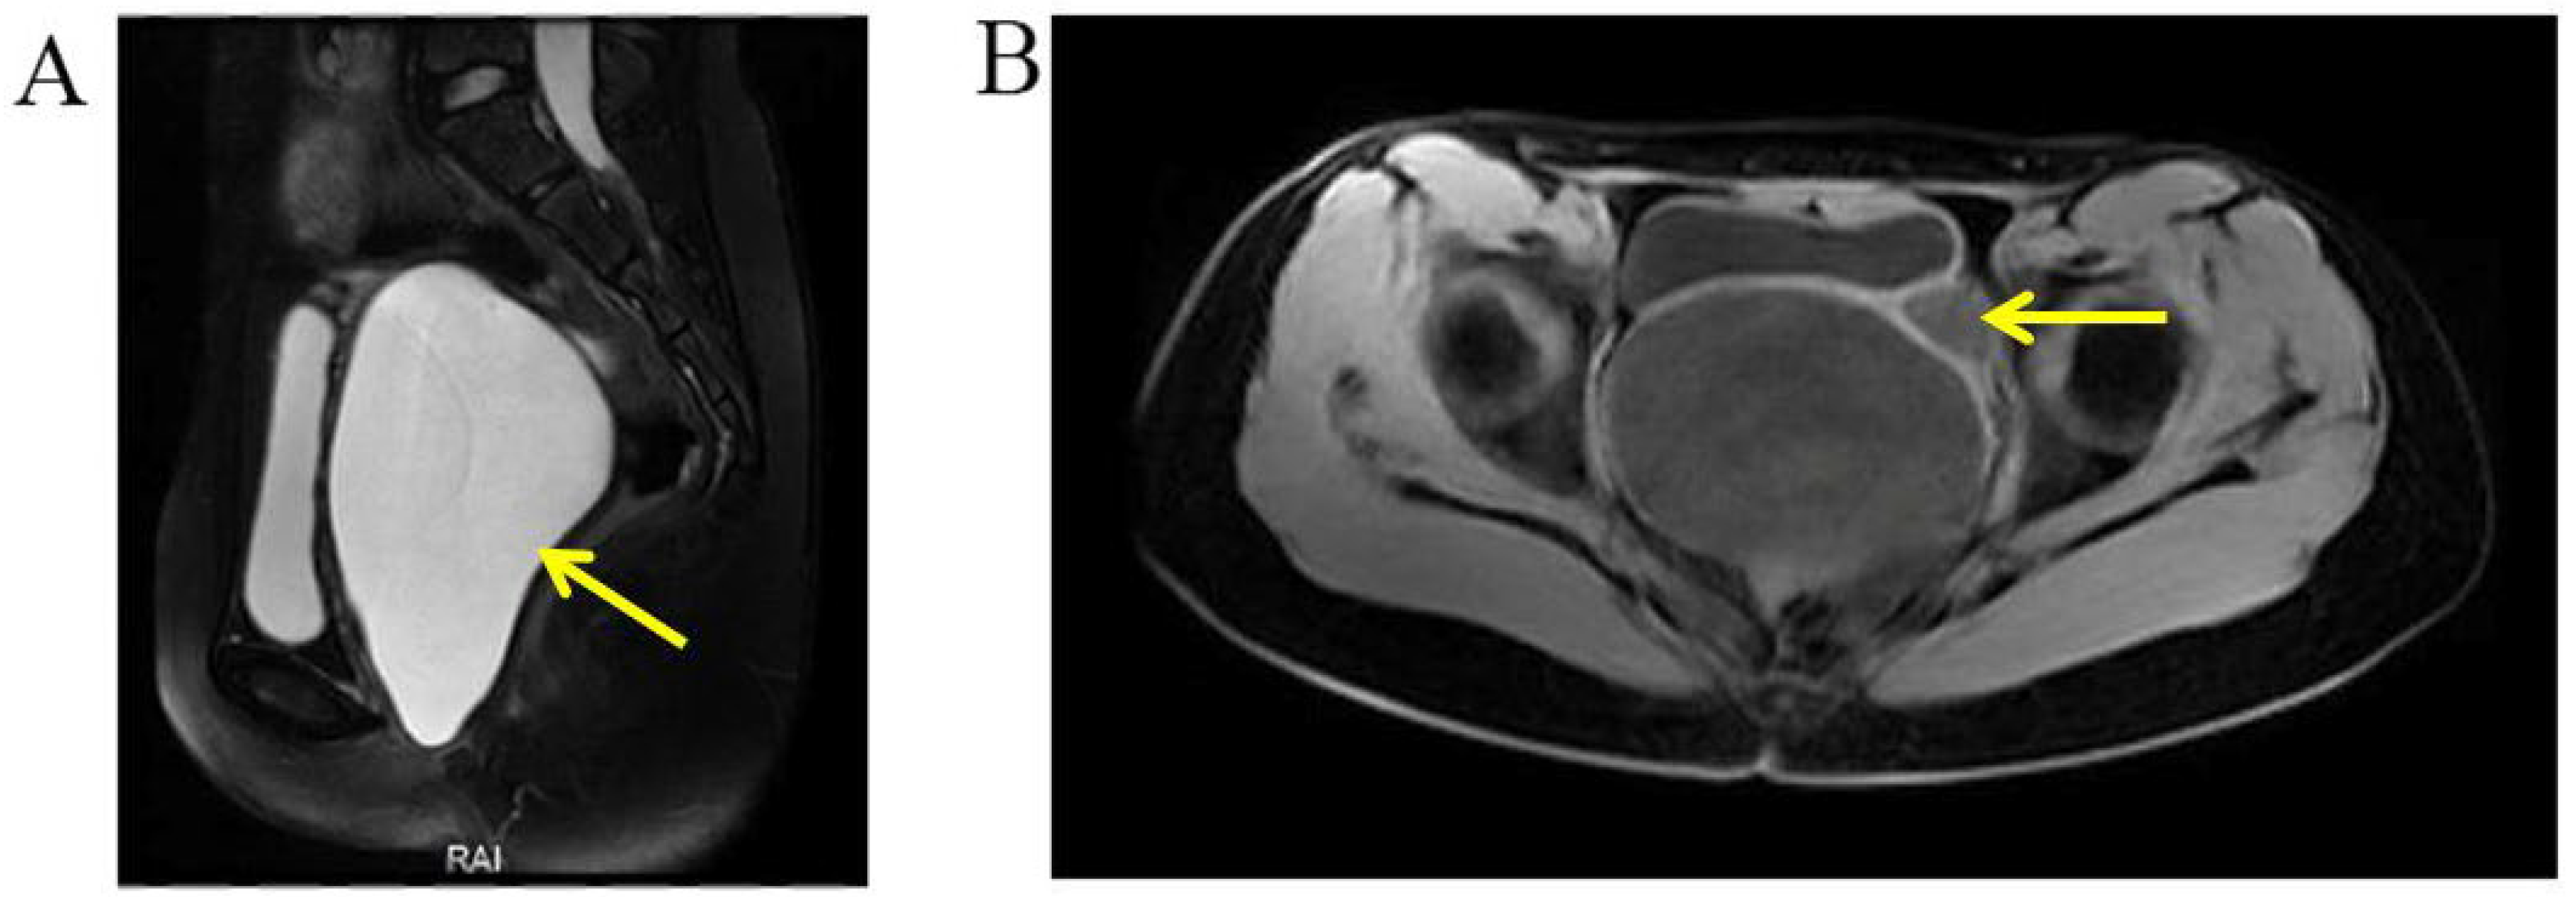

Selected MRI images of the pelvis. (A) Pelvic MRI demonstrated a highly dilated vagina with internal fluid measuring 10.2 × 7.3 × 13.2 cm (yellow arrow). (B) Left ureter was dilated (yellow arrow), and the ectopic orifice of the left ureter was located at the vagina.

A 14-year-old girl was admitted to the department of gynecology due to monthly cyclic pelvic pain. A pelvic examination showed an imperforate hymen. A rectoabdominal examination showed a cyst 10 cm in diameter palpated in the pelvis. Additionally, the bottom edge of the cyst was located 1 cm away from the vaginal opening. The needle aspiration fluid through the hymen revealed values of 5213.2 μmol/L for creatinine and 39.63 mmol/L for urea. An abdominal MRI revealed a left pelvic cystic mass, left hematosalpinx, and left kidney atrophy (Figure 6). The pelvic MRI demonstrated that the fluid-filled vagina was highly dilated, and the left dilated ureter drained into the vagina (Figure 7). An ascending urography also revealed a left ectopic ureter. After the incision of the imperforate hymen, 500 mL of pale-yellow purulent pus drained from the vagina. After an antibiotic treatment, a laparoscopy and hysteroscopy were performed. The surgical procedures revealed a double primordial uterus measuring 2.5 × 1.9 cm on the right and 3.0 × 1.5 cm on the left, but no cervix. Bilateral ovaries and fallopian tubes were normal. The patient’s vagina was unobstructed. An opening orifice of the left ureter, with a diameter of 0.2 cm, was seen in the vagina. Subsequently, the left atrophic kidney and the irregularly enlarged left ureter were removed to prevent future leakage and infection. In summary, the left ectopic ureter opened into the vagina, causing fluid leakage into the vagina. Due to the imperforate hymen, urine accumulated inside the vagina, which led to vaginal dilatation, infection, and pelvic pain.

Figure 6.

MRI demonstrated the atrophy of left kidney.